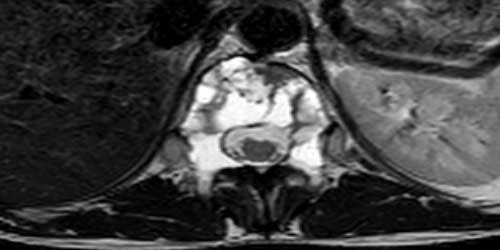

- Manyetik rezonans görüntüleme (MRG). MRG, omurga, omurilik ve sinirlerinizin doğru görüntülerini üretmek için güçlü bir mıknatıs ve radyo dalgaları kullanır. MRG genellikle vertebral tümörleri teşhis etmek için tercih edilen testtir. Belli dokular ve yapıları vurgulamaya yardımcı olan bir kontrast madde, test sırasında ayağınızdaki veya önkoldaki bir damar içine enjekte edilebilir.